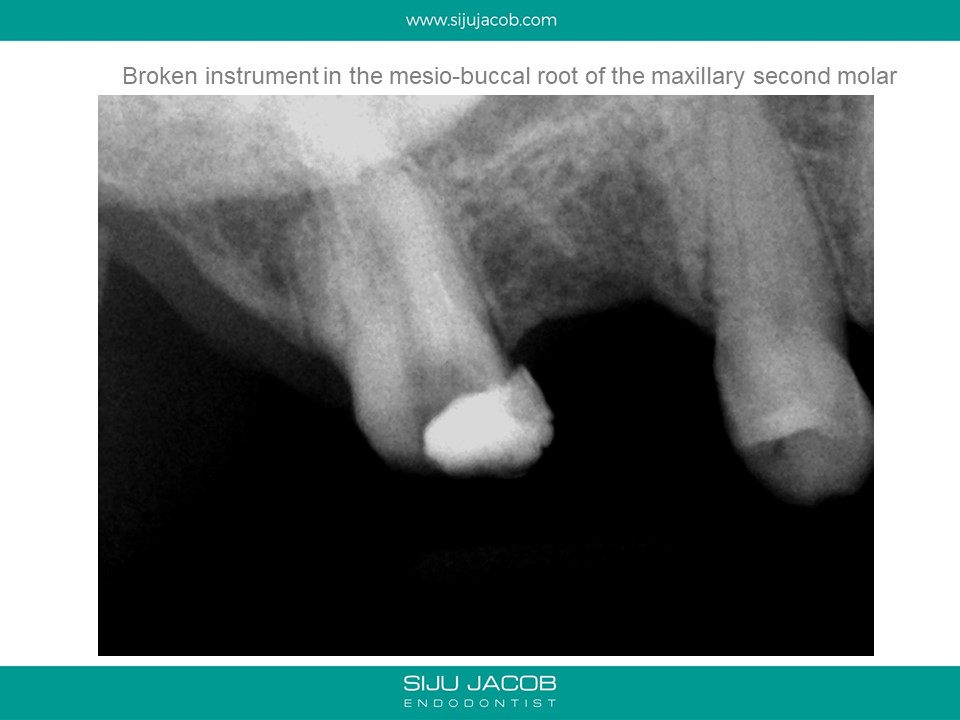

The previous practitioner fractured an instrument in the mesio-buccal root and referred this case. Instrument retrieval is usually fast and quite predictable in locations like the middle and coronal thirds.